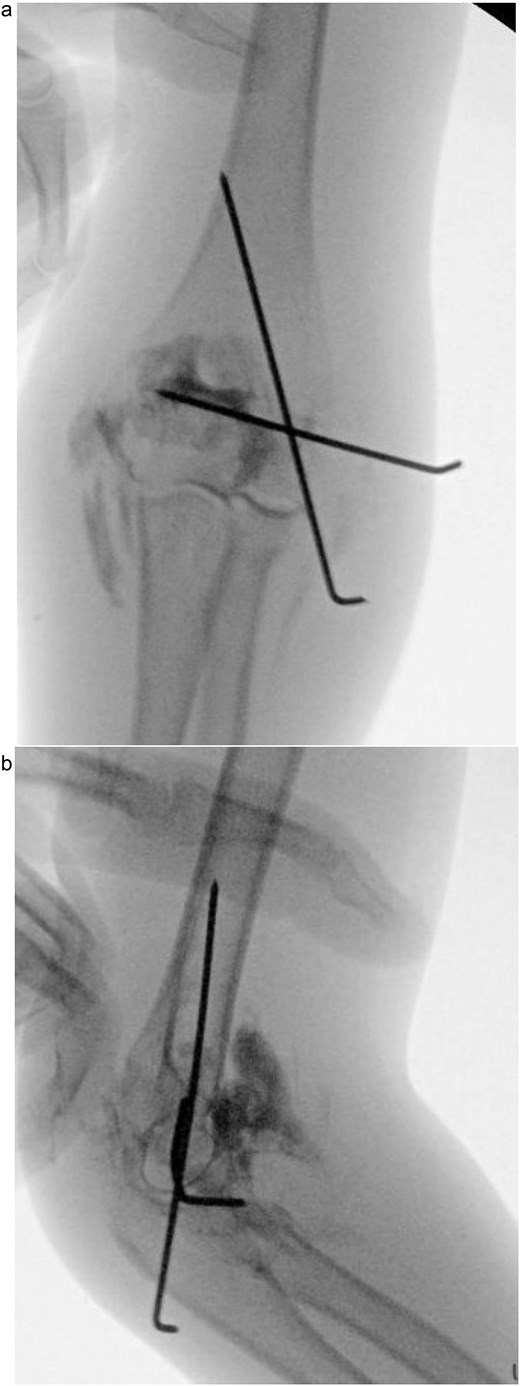

Under procedural sedation, closed reduction of the elbow dislocation was performed, restoring joint alignment and stability. However, post-reduction imaging showed persistent displacement of the lateral condyle fragment (Fig. 2a). The patient was subsequently taken to the operating room, where closed reduction of the condylar fracture was carried out under general anesthesia. As post-reduction displacement was less than 2–4 mm with intact articular cartilage, fixation was performed using two smooth Kirschner wires under fluoroscopic guidance. An arthrogram confirmed joint congruity and cartilage integrity (Fig. 3a). A long-arm posterior slab was applied with the elbow in <90° of flexion to minimize the risk of compartment syndrome (Fig. 4a).

(a) Immediate post-reduction anteroposterior radiograph showing restored joint alignment with persistent lateral condyle displacement. (b) Lateral view confirming maintained reduction of the ulnohumeral joint and residual separation of the lateral condyle fragment.

(a) Intraoperative fluoroscopic image following closed reduction and K-wire fixation showing anatomical alignment of the lateral condyle. (b) Arthrogram confirming a congruent articular surface and stable fixation of the fracture fragment.

(a) Postoperative anteroposterior radiograph demonstrating stable fixation of the lateral condyle with two smooth Kirschner wires. (b) Lateral view showing proper wire placement and a well-aligned elbow maintained in a posterior slab splint.